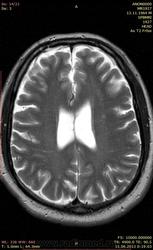

Увы, анамнез известен только со слов: у пациента месяц назад якобы был эпизод нарушения речи и слабости в правых конечностях, что вызвало желание исключить ОНМК. На сегодняшний день таких жалоб нет.

1. Что чернеет в базальных ядрах (бледные шары, красные ядра)? Железо?

2. Что за очаги в белом веществе - в основном перивентрикулярно, а также в стволе и мозжечке? Обычные проявления ДЭП? Или демиелинизация другого генеза?

С чем мы вообще имеем дело? Болезнь Галлервордена-Шпатца начинается, как правило, в молодом возрасте... Болезнь Крейцфельда-Якоба? Паркинсона? Гентингтона? Другая нейродегенеративная патология?

смею предположить что описаные и представленные изменения это лейкоэнцефалопатия, вероятнее всего сосудистого характера, а морфологический субстрат изменений кистозно-глиозные очаги как исход лакунарных ишемических инфарктов. Я не мрт-шник, могу ошибаться)

Совершенно верно. Это все так. Но необычность в том, что помимо указанных вами изменений, здесь имеет место явное понижение сигнала на Т2 от бледных шаров и красных ядер, что говорит об отложении железа. Еще лучше это видно на Т2*GRE. Такая картина обычно бывает при болезни Галлервордена-Шпатца, но загвоздка в том, что эта болезнь манифестирует в детском или молодом возрасте, а пациент уже явно не молод. Есть и другие причины такого депонирования железа, о которых я упомянул, и о которых хотел бы услышать какие-нибудь мнения.